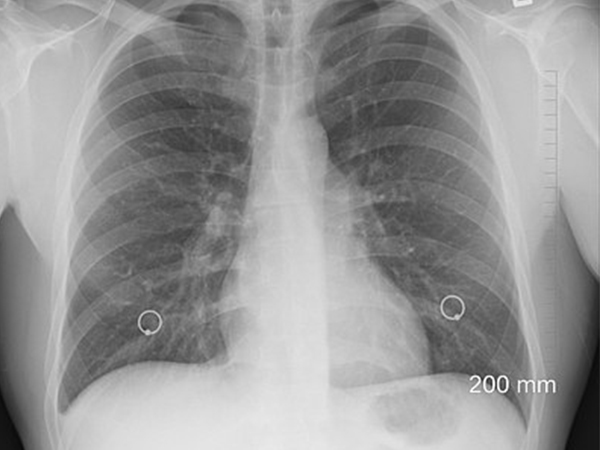

ఎలా కనుగొనాలి

గుండె కణితులను గుర్తించడం చాలా కష్టం. ఎందుకంటే ఇది చాలా అరుదు మరియు దాని లక్షణాలు ఇతర గుండె జబ్బుల లక్షణాలతో కూడి ఉంటాయి. ప్రాధమిక గుండె కణితులను గుండె ఆగిపోవడం,

అరిథ్మియా లేదా వివరించలేని గుండె వైఫల్యం ఉన్నవారికి పరీక్షించడం ద్వారా నిర్ధారణ చేయవచ్చు.

శరీరంలోని ఇతర ప్రాంతాలతో బాధపడుతున్నవారిలో గుండె ఆగిపోయే సంకేతాలు వ్యక్తమవుతున్నాయి. గుండె తదుపరి పరీక్షలో టైప్ II గుండె కణితులు ఉన్నట్లు తెలుస్తుంది. గుండె కణితులను గుర్తించే

పరీక్షలు:

* రొమ్ము ఎక్స్-రే

* ఎకోకార్డియోగ్రామ్

* హార్ట్ ఎంఆర్ఐ

* కరోనరీ యాంజియోగ్రఫీ

* రక్త పరీక్షలు

* టోమోగ్రఫీ

* ఎలక్ట్రో కార్డియోగ్రామ్